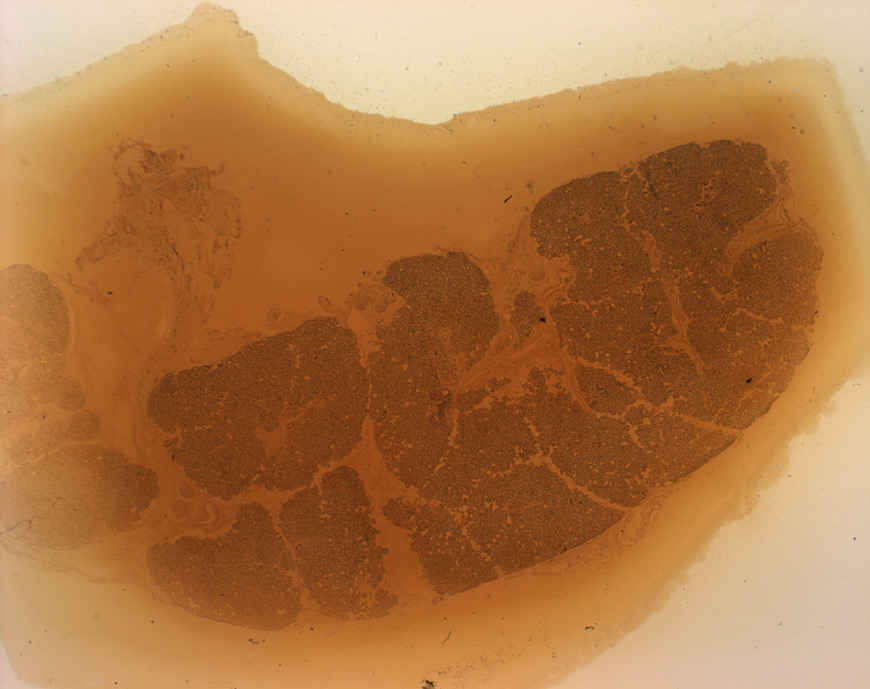

Die Tränendrüse (Gl. lacrimalis) produziert einen Großteil der Tränenflüssigkeit (zusammen mit den Gll. tarsales).

Sie liegt in der Orbita dem Auge kraniolateral auf. Sie ist eine tubulo-alveoläre Drüse ohne Schalt- und Streifenstücke.

Histologisch könnte man die Tränendrüse mit einer der großen Speicheldrüsen (v.A. Gl. parotidea) verwechseln, doch gibt es Unterschiede:

- keine Streifen- und Schaltstücke

- tuboalveoläre Endstücke

- wenig bis keine Fettzellen

Das Fehlen von Streifen- und Schaltstücken erklärt auch wieso Tränenflüssigkeit isoton ist, da in diesen Abschnitten Cl- und Na resobiert werden (vgl. Gl. parotidea)

in der Mitte dürfte ein Ausführungsgang sein, denn in der Lacrimalis sind keine Streifen- oder Schaltstücke vorhanden. Man sieht aber auch flache Endothelzellkerne am inneren Rand des Lumens, was auch für ein Blutgefäß sprechen könnte.

Anmerkung zum Hotspot: Zudem gibt es in der Tränendrüse keine Schalt- und Streifenstücke (s. Präparatbeschreibung)